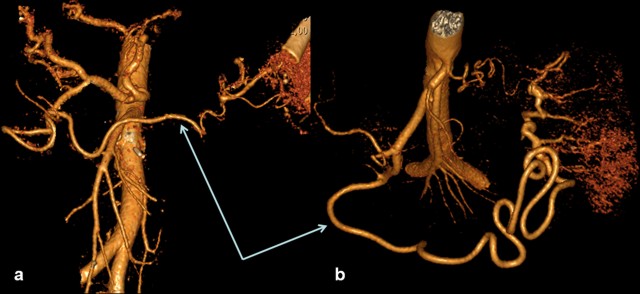

CT Angiography

Preceding surgery, the splenic artery was always seen on CT angiography as a thick stem with no other branches travelling to the spleen (Figures 7a and 8a). As a consequence of splenic artery resection, the whole or the bulk of its trunk were no longer available for evaluation by CT angiography after a spleen-preserving distal pancreatectomy with resection of the splenic vessels and, in all 10 cases, the gastroepiploic arcade was seen to have become the “highway” to the spleen within 7-30 days after surgery (Figures 7b, 8b, and 9). In two cases, due to technical reasons, 3D CT angiography was only carried out postoperatively but, in both cases, there were no doubts about the source of the blood supply to the spleen (Figure 9). In none of the 10 cases was any appreciable blood flow through the short gastric arteries visualized.

Thus, 3D CT angiography after a spleen-preserving distal pancreatectomy with resection of the splenic vessels did not reveal any reliable blood flow via the short gastric arteries. In all cases, the dominant role of the left gastroepiploic artery serving as the main blood supply to the spleen through the gastroepiploic arcade was observed.

Figure 7. Celiaco-mesenterial anatomy in а 53-year-old man with chronic pancreatitis of the distal type. 3D CT angiography after the renal artery images were eliminated. Vertical view. a. Before surgery: the splenic artery thick trunk with no collaterals is shown. b. Fourteen days after a spleen-sparing distal pancreatectomy with resection of the splenic vessels: the spleen is fed through the gastroepiploic arcade. There are no other detectable major arteries to feed the spleen. D: drainage tube; GEA: gastroepiploic arcade; RGEA: right gastroepiploic artery; SA splenic artery; SAR: splenic artery remnant |

Figure 8. Celiaco-mesenterial anatomy in а 59-year-old woman with a neuroendocrine tumor of the pancreatic body and tail. 3D CT angiography after the renal artery images were eliminated. a. Before surgery: the splenic artery thick trunk with no collaterals is shown. b. Ten days after a spleen-sparing distal pancreatectomy with resection of the splenic vessels: the spleen is fed through the gastroepiploic arcade. There are no other detectable major arteries to feed the spleen. c. After surgery, vertical view: the arrow is pointing to the gastroduodenal artery, i.e., the site of origin of the gastroepiploic arcade. GEA: gastroepiploic arcade; LGEA: left gastroepiploic artery; SA: splenic artery |

Figure 9. Celiaco-mesenterial anatomy in 57 (a.) and 51 year old females (b.) women with mucinous cystic tumors of the pancreatic body and tail. 3D CT angiography 7 and 30 days, respectively, after a spleen-sparing distal pancreatectomy with resection of the splenic vessels without the renal artery images. The only vessels feeding the spleen are the gastroepiploic arcades (arrows). There are no other detectable collaterals of value. 3D CT angiography images were not obtained before surgery. |